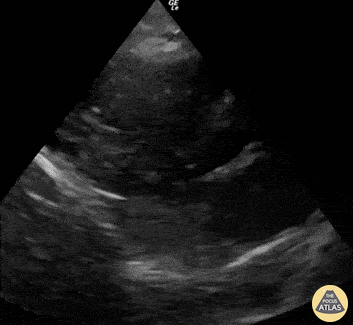

This is a PLAX view obtained during CPR . It reveals adequate compressions with the LV “squashing” and obliterating the LV lumen; then subsequently the LV lumen reappearing and recoiling, which allows the LV to refill. Renato Tambelli, @JediPocus